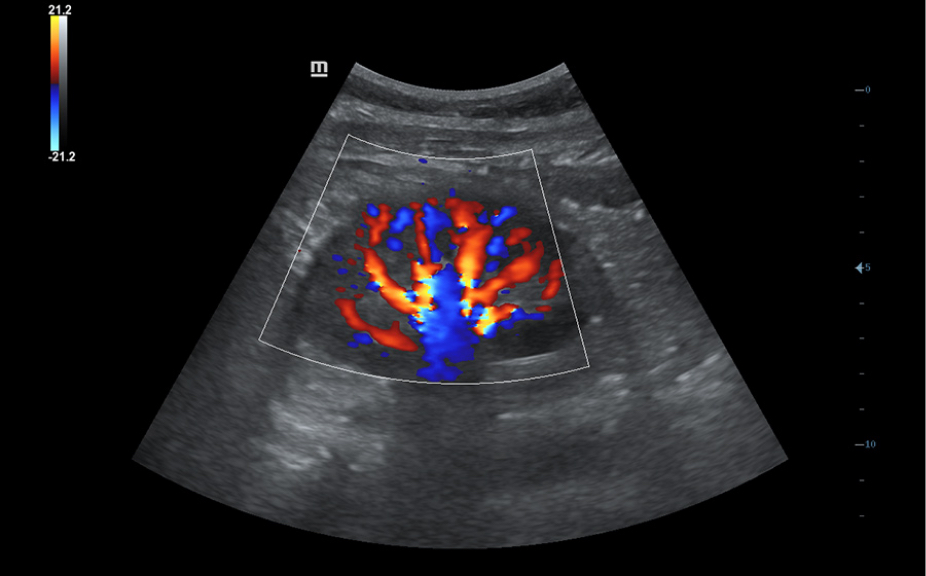

Normale anatomische illustraties met inbegrip van schematische beelden en ultrasoundbeelden.

Zijdelingse weergave van een standaard ultrasonogram dat visuele aanwijzingen geeft over de relevante gebieden.

Standaard ultrasoundbeelden

3

Vergelijking realtimescan ter referentie.